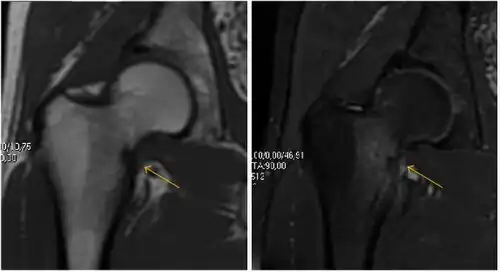

MRI has been shown to have 100% sensitivity and specificity in prospective studies of occult hip fractures. These fractures were diagnosed by bone marrow edema and a low signal fracture line, mainly on T1 or T2 weighted images (Figure 10).[1]

Figure 10:

Stress femoral neck fracture in a young athlete barely visible in X-ray film as a sclerotic line (arrow)[1] -

In this case, Tc 99 scintigraphy shows a band of uptake[1] -

Furthermore, T1 (left) and DP fat saturated (right) weighted MR images showed the fracture line and a pattern of edema.[1]